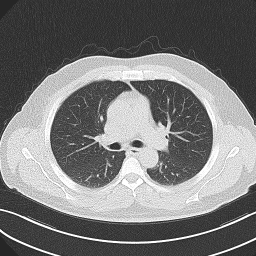

• Lung Cancer CT Dataset (LCT) [35]: From different specialist hospitals, the IQ-OTH/NCCD lung cancer dataset was collected over three months in the fall of 2019. It comprises CT scans from patients with lung cancer in different stages and healthy subjects, totaling 1190 images from 110 cases. The dataset, marked by oncologists and radiologists, categorizes cases into three classes: normal (55 cases), benign (15 cases), and malignant (40 cases).

The proposed QMedShield’s security is evaluated using a number of metrics and proved that it is resistant to various cryptographic attacks including brute-force attacks, statistical attacks, histogram attacks, and differential attacks. Throughout the section, 6 sample medical images BMRI1,BMRI2,CXR1,CXR2,LCT1,LCT2𝐵𝑀𝑅subscript𝐼1𝐵𝑀𝑅subscript𝐼2𝐶𝑋subscript𝑅1𝐶𝑋subscript𝑅2𝐿𝐶subscript𝑇1𝐿𝐶subscript𝑇2BMRI_{1},BMRI_{2},CXR_{1},CXR_{2},LCT_{1},LCT_{2} are taken (2 images from each dataset) to show the performance comparison. The selection of MRI, X-ray, and CT images for the encryption task aims to demonstrate the versatility and effectiveness of our model across various imaging modalities, showcasing its applicability and robustness in diverse clinical scenarios. Figure 11 shows the selected sample medical images and their corresponding encrypted images.

Refer to caption

(a) BMRI1𝐵𝑀𝑅subscript𝐼1BMRI_{1}

(b) CXR1𝐶𝑋subscript𝑅1CXR_{1}

(c) LCT1𝐿𝐶subscript𝑇1LCT_{1}

(d) BMRI2𝐵𝑀𝑅subscript𝐼2BMRI_{2}

(e) CXR2𝐶𝑋subscript𝑅2CXR_{2}

(f) LCT2𝐿𝐶subscript𝑇2LCT_{2}

(g) E(BMRI1)𝐸𝐵𝑀𝑅subscript𝐼1E(BMRI_{1})

(h) E(CXR1)𝐸𝐶𝑋subscript𝑅1E(CXR_{1})

(i) E(LCT1)𝐸𝐿𝐶subscript𝑇1E(LCT_{1})

(j) E(BMRI2)𝐸𝐵𝑀𝑅subscript𝐼2E(BMRI_{2})

(k) E(CXR2)𝐸𝐶𝑋subscript𝑅2E(CXR_{2})

(l) E(LCT2)𝐸𝐿𝐶subscript𝑇2E(LCT_{2})

Figure 11: Selected sample plain medical images and the corresponding encrypted cipher images